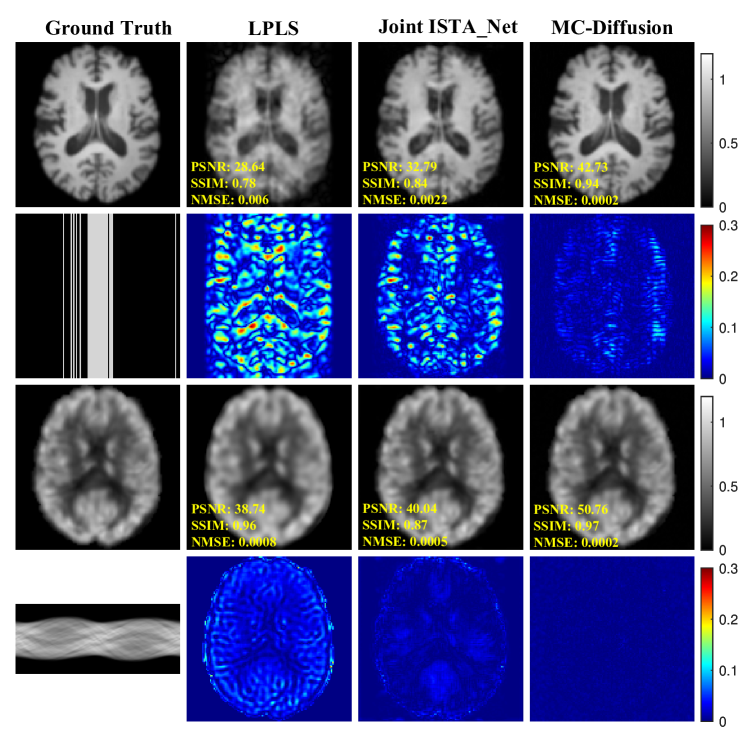

Figure 4 illustrates the reconstruction outcomes of various methods with a Cartesian undersampling factor of 3. The results clearly show that MRI reconstructed using the LPLS method exhibits severe artifacts, while Joint ISTA Net introduces aliasing patterns in its reconstructions. Table 3 complements these visual observations with quantitative metrics, further validating the effectiveness of our proposed approach.

Refer to caption

Figure 4: Joint reconstruction results under cartesian undersampling at 3-fold and for sinograms of size 128×300128300128\times 300128 × 300. The values in the corner are each slice’s PSNR/SSIM/NMSE values. The first row describes the ground truth of MRI and the results of reconstruction by contrast models. The second row shows MRI undersampling patterns and error views. The third row describes the ground truth of PET and the results of joint reconstruction by contrast models. The fourth row shows PET sinogram data and error views. The grayscale of the reconstructed images and the error images’ colour bar are on the figure’s right.

Table 3 presents quantitative metrics that compare the reconstruction results of all methods using 3-fold MRI and PET undersampling. It is evident that the proposed method outperforms the comparison methods by a significant margin in terms of the quantitative metrics. This observation underscores the effectiveness of the proposed method in addressing the joint reconstruction problem.

Figure 5 depict the joint reconstruction results with 4-fold MRI undersampling. The images were reconstructed using LPLS, Joint-ISTA-Net, and MC-Diffusion. The average quantitative metrics for the ADNI dataset are presented in Table 4. MC-Diffusion achieves the highest PSNR and SSIM in all the compared methods. Similarly, MC-Diffusion attains the lowest NMSE in all the compared methods.

Figure 5: Joint reconstruction results under cartesian undersampling at 4-fold and for sinograms of size 128×300128300128\times 300128 × 300. The first row describes the ground truth of MRI and the results of reconstruction by contrast models. The second row shows MRI subsampling patterns and error views. The third row describes the ground truth of PET and the results of joint reconstruction by contrast models. The fourth row shows PET sinogram data and error views.